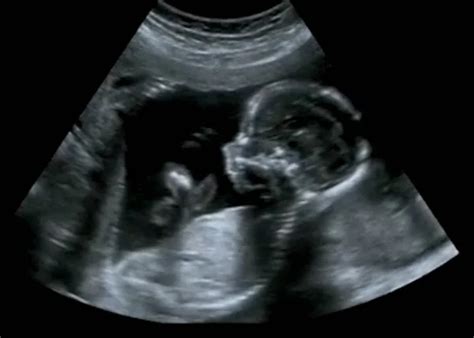

Az első ultrahang vizsgálat során a legfontosabb cél a terhesség tényének megállapítása, a méhen belüli elhelyezkedés ellenőrzése és a petezsák méretének felmérése. A petezsák a terhesség korai szakaszában az embrió fejlődésének első látható jele. Az 5. hét végén a petezsák jelenik meg, ezt keresik a méhben, mert ez lesz a kis embriócsomó otthona. Az ultrahang képen ez egy jól körülhatárolható kis fekete folt lesz a szürkés színű háttérben. Megállapítják, hogy jó helyen található-e, nincs-e méhen kívüli terhesség.

A petezsák mérete önmagában nem mindig árulkodik a terhesség egészséges vagy problémás voltáról. Fontosabb a fejlődés üteme és az embrió megjelenése. A petezsákban nagyjából a 6. hétben láthatóvá válik a szikhólyag, ami a kis embrió táplálásáért felelős, amíg a méhlepény át nem veszi a szerepét. Önmagában azonban sem a petezsák, sem a szikhólyag jelenléte még nem garantálja, hogy van-e, lesz-e benne embrió.

A terhesség tényét akkor állapítják meg, amikor már az embriócsomó is látható a szikhólyagban és a szívkezdeménye dobog. Ez általában a 6-7. terhességi hét környékén, de késői peteérés esetén nem ritkán csak a 8. héten történik meg. Egy (megtermékenyülést követő) 4 hetes terhesség, olyan, mint egy 6 hetes (utolsó menses első napjától, ha nem gondolunk rendszertelen ciklusra) terhesség. Tehát, ha az orvos 4-5 hetes terhességet állapít meg, és még csak a petezsák és a szikhólyag látható, az teljesen normálisnak tekinthető.

Az első ultrahang vizsgálat általában a várandósság 6-8. hetében történik, amikor már remélhetőleg látható az embrió és hallható a szívhangja. Ha az első vizsgálat a 4-5. hét környékén történik, és még csak a petezsák és a szikhólyag látható, az nem ok az aggodalomra. A legfontosabb, hogy a következő kontroll vizsgálaton látható legyen a fejlődés.